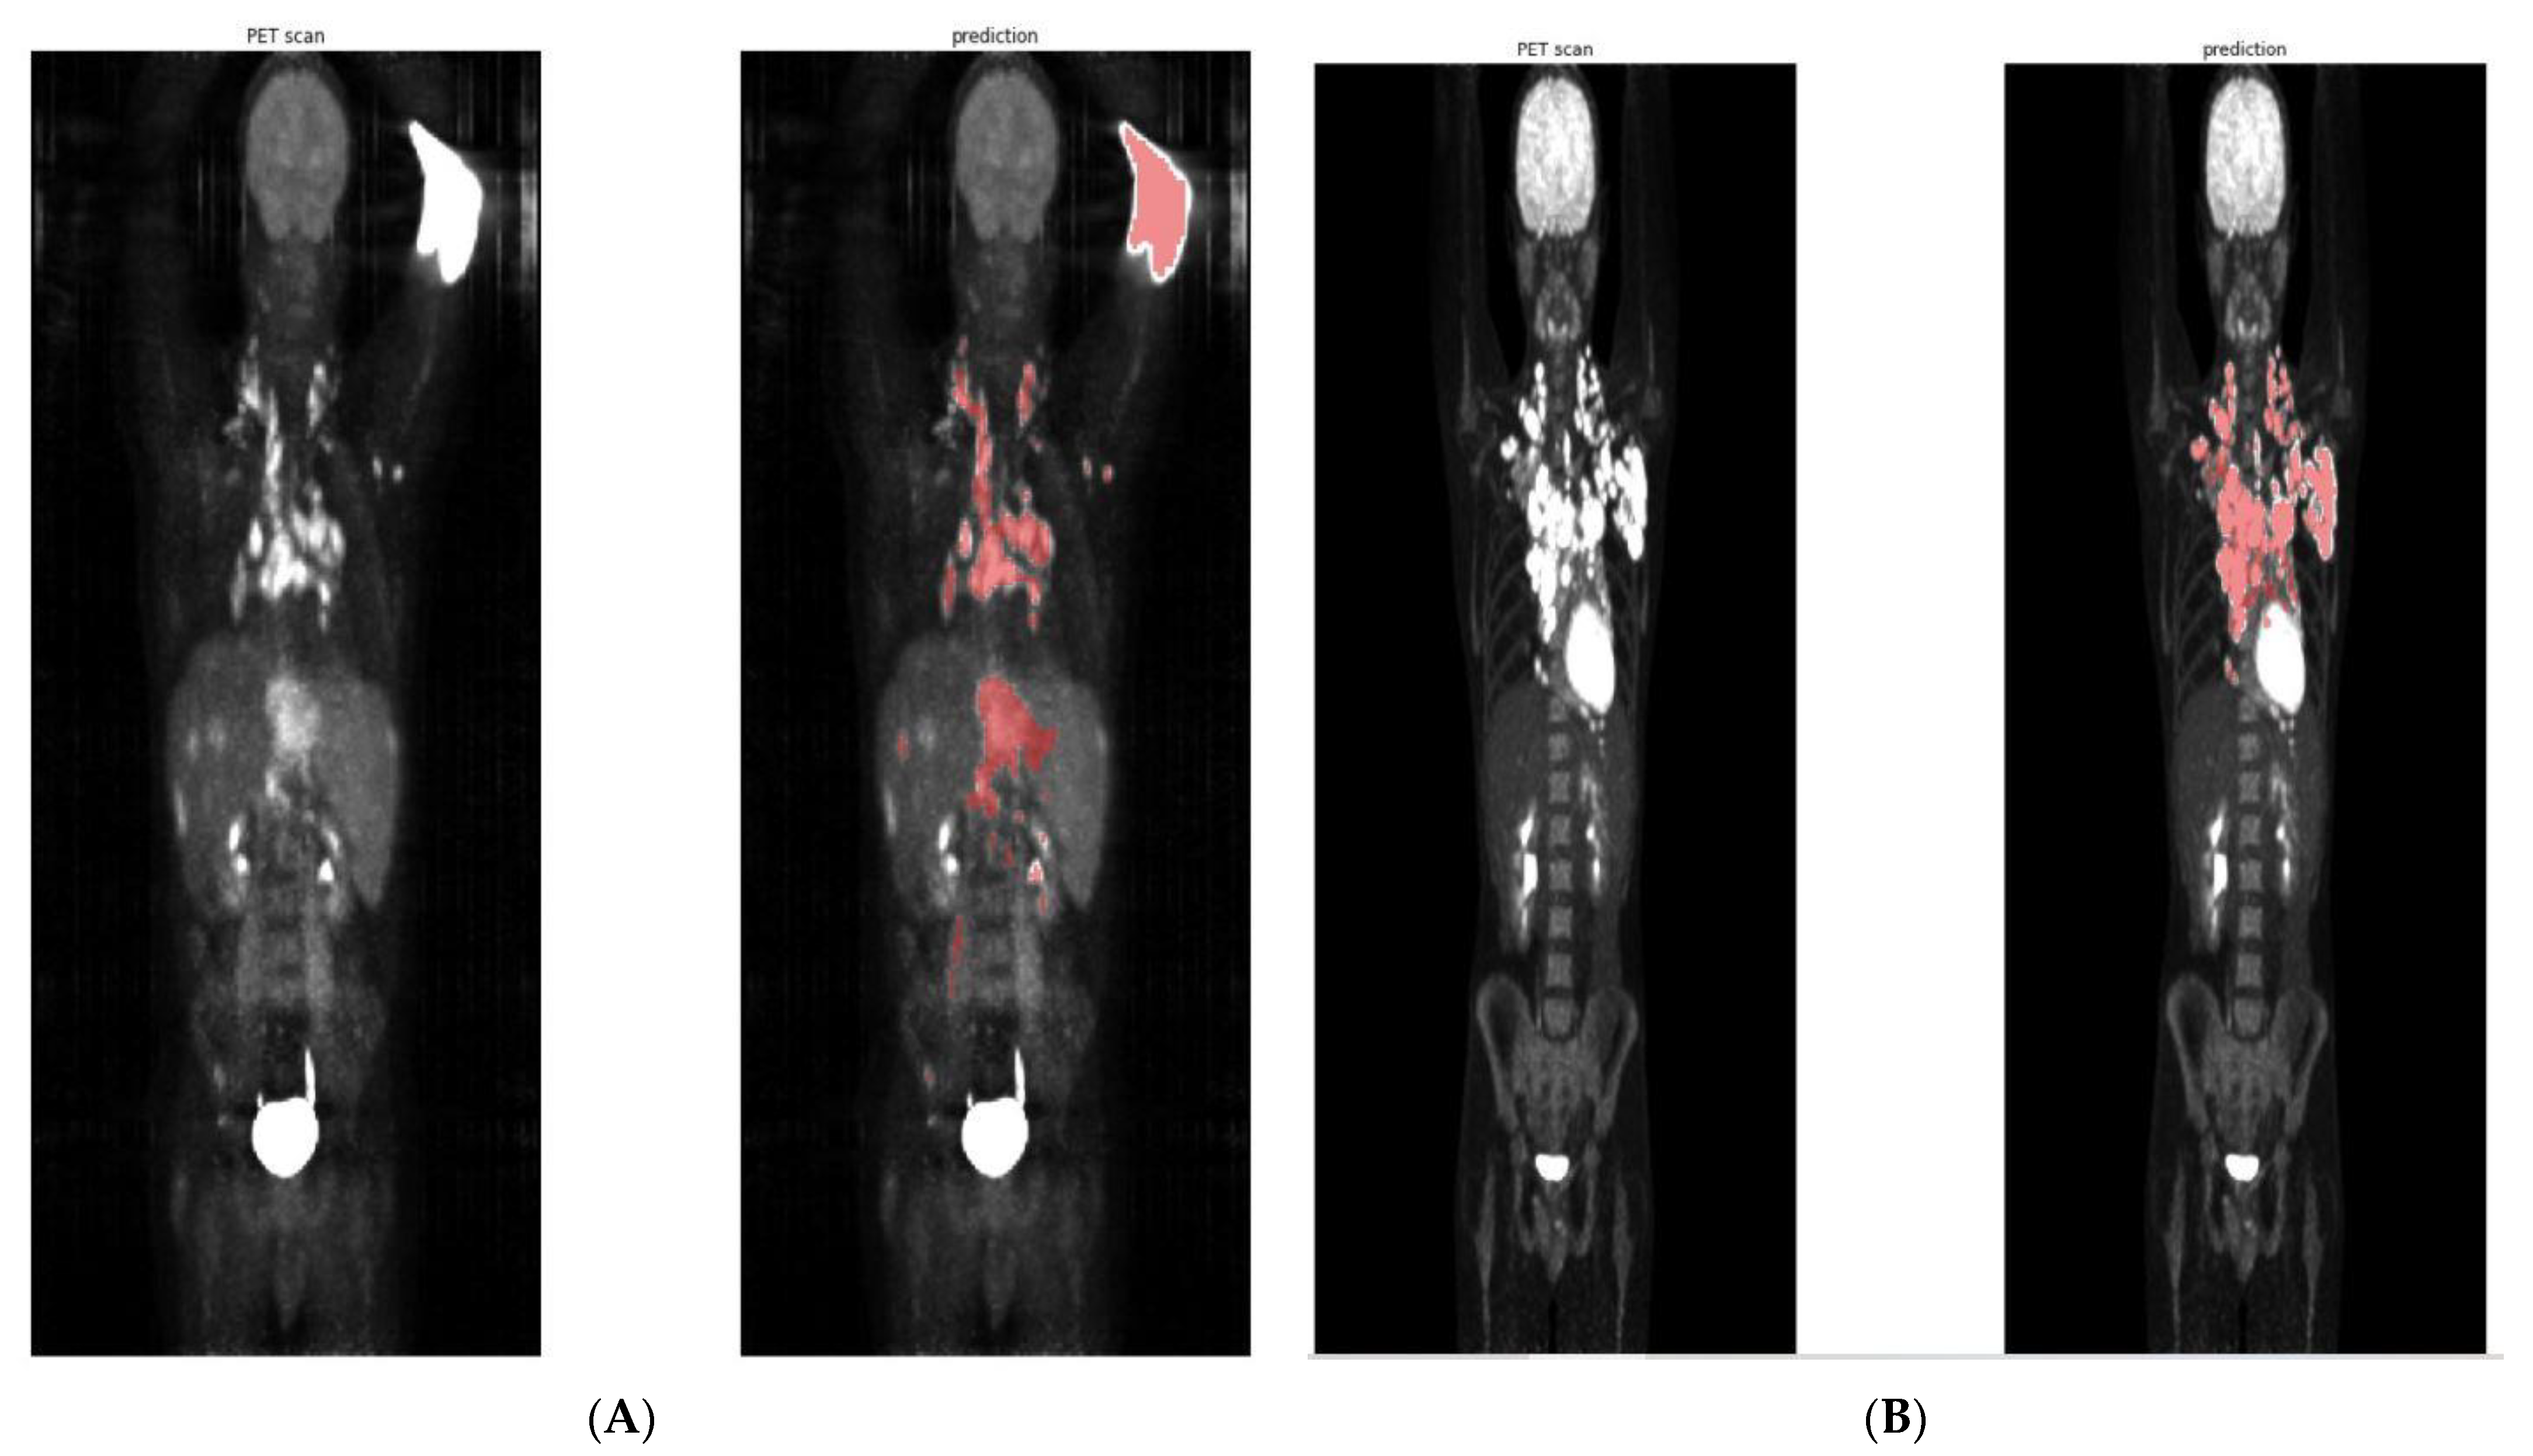

3.2. Raw TMTV Prediction without Post-Processing

3.3. Clustering of Predicted Segmentation for 41% TMTV Calculation